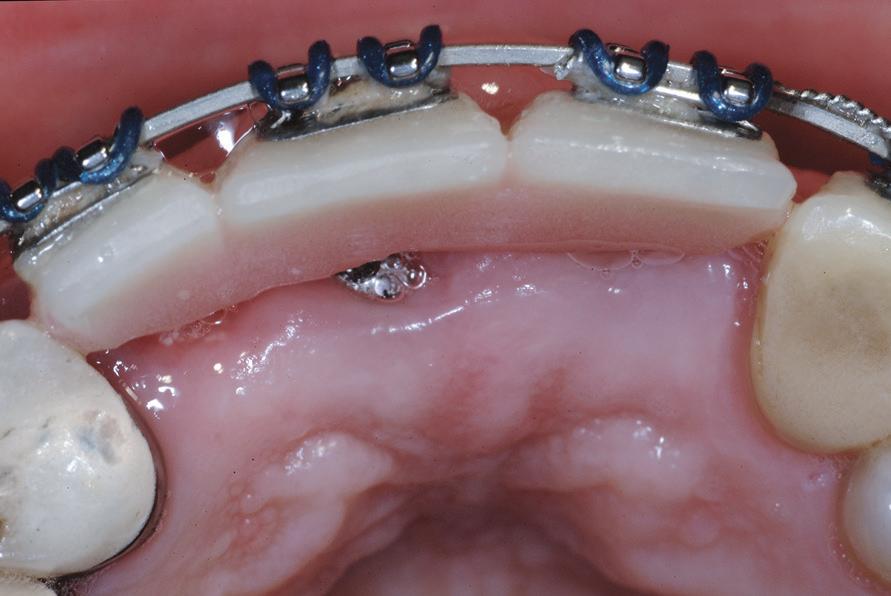

Pentru tracționarea dinților impactați, este importantă utilizarea fie a unui arc de sârmă cu bază dreptunghiulară din oțel inoxidabil, fie o bară transpalatinală groasă, cu rigiditate adecvată. Acest lucru este esențial în special la caninii incluși palatinal. Evitarea utilizării arcurilor flexibile poate permite un control mai bun al efectelor adverse asupra dinților adiacenți în timpul tracțiunii. Se poate obține o ancorare suficientă în interiorul arcadei, prelucrând secvența până la arcurile 0,019 x 0,025 într-un slot de 0,022. Acest lucru previne deformarea arcurilor, deschiderea ocluziei din cauza tracțiunii, intruziunea dinților adiacenți și alte efecte adverse conexe. S-au utilizat diferite elemente externe, cum ar fi porțile batante, arcurile transpalatinale, extensoarele Hass, arcurile guad helix, expansoarele Hyrax și dispozitivele de ancorare temporară (temporary anchorage devices, TAD), ca aparate de ancorare alternative. În cazul unei bare transpalatinale, obiectivul este de a utiliza brațele de extensie în consolă pentru a tracționa caninul impactat în palat. Aceasta este urmată de tracțiunea caninului în poziția sa finală, utilizând arcuri de poziționare sau alte metode pentru a aduce dintele inclus pe arcada dentară (fig. 4, 5).

Figurile: 4. Accesoriu de tipul porții batante utilizat pentru tracționarea directă a unui canin palatinal gestionat cu expunere deschisă.

5. Expunerea deschisă a unui canin cu impactare palatinală; s-a utilizat o bară transpalatinală ca sursă de ancorare cu un braț extensibil conceput pentru tracțiune directă.

6, 7. Utilizarea lamboului repoziționat apical pentru a gestiona caninii bilaterali cu impactare facială. După expunere, s-a practicat și frenectomia și au fost plasate bracketuri bilaterale (fig. 6). S-a realizat tracțiunea ortodontică, ce a permis poziționarea corespunzătoare a ambilor canini pe arcada superioară (fig. 7)

apoi direcționarea vestibulară a caninului (fig. 8, 9).